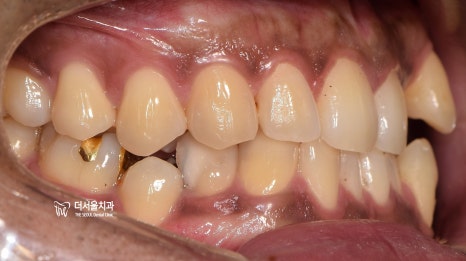

『초진 사진』

정면과 측면에서의 모습입니다.

치열의 불규칙성이 한 눈에 들어옵니다.